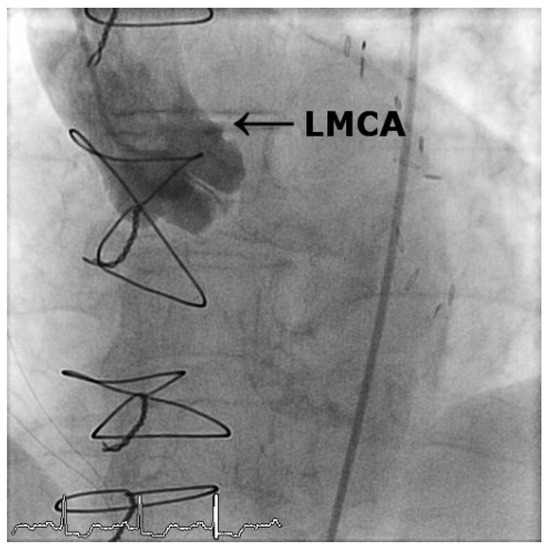

Case2